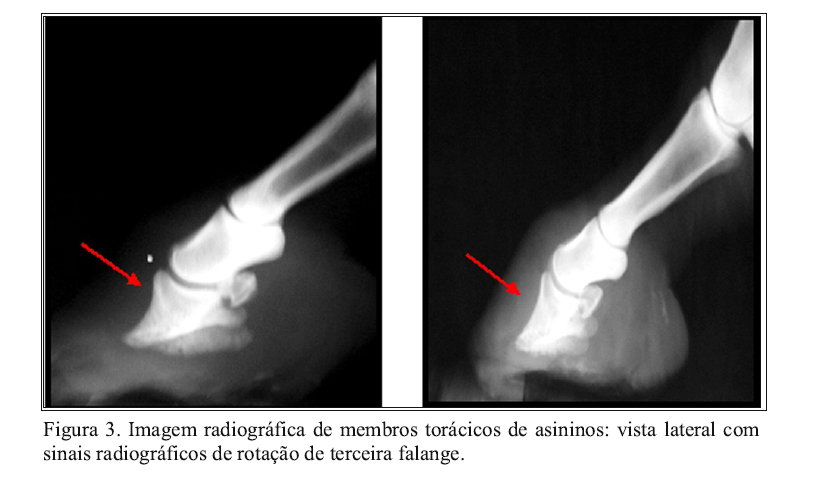

A rotação de falange constituiu uma lesão observada em 17,50% (n=07) dos animais, sendo que em 5% (n=02) bilateralmente, o que é associado ao aumento do espaço intra-articular (Figura 3). A angulação da rotação de falange dos animais acometidos variou de 7 a 10 graus. Entretanto, os animais que apresentaram essa alteração estavam em plena atividade de trabalho e não evidenciaram grau de claudicação superior ao grau 2, o que mostra uma maior resistência dos asininos utilizados em veículos de tração.